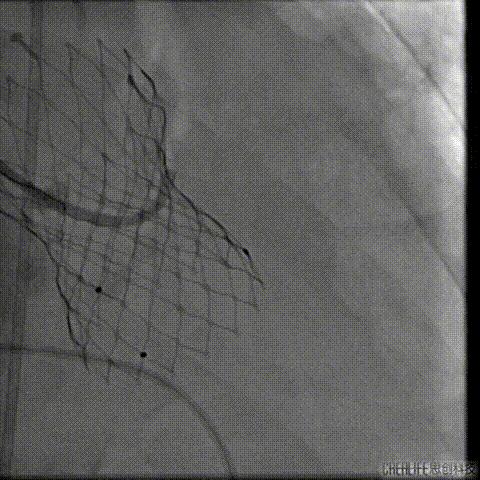

置入Venus-A32号瓣膜并释放

复查造影

撤出冠脉保护

再次复查造影